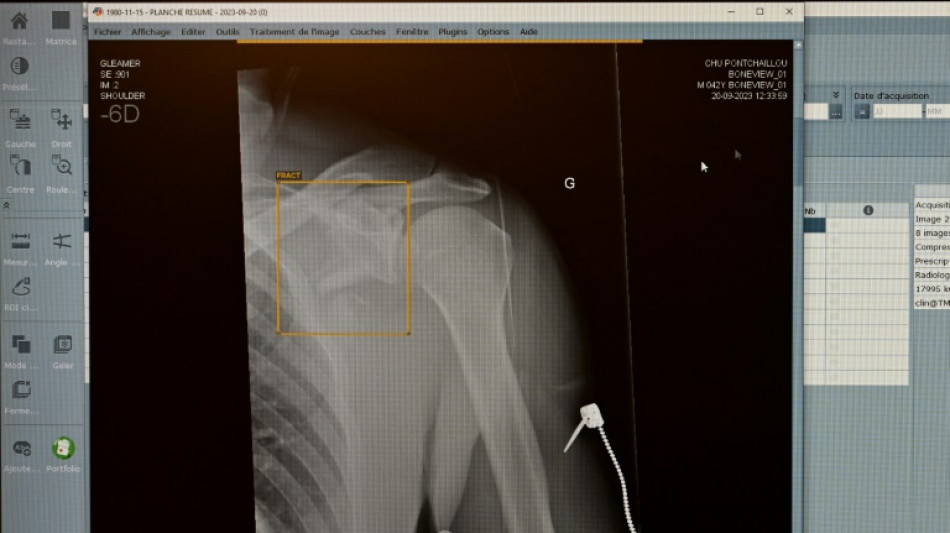

TÜV-Verband: Weniger Röntgengeräte mit Mängeln - Risiken bleiben aber / Foto: Damien MEYER - AFP/Archiv

Jedes achte vom TÜV im vergangenen Jahr geprüfte medizinische Röntgengerät hat Mängel aufgewiesen. Die Gutachter stellten an 1893 der insgesamt rund 15.600 untersuchten Röntgengeräte Mängel wie etwa unzureichend gekennzeichnete Kontrollbereiche fest, wie der TÜV-Verband am Mittwoch in Berlin mitteilte. Die höchste Mängelquote wiesen Röntgengeräte in Zahnarztpraxen auf.

Insgesamt sank der Anteil der festgestellten Mängel im Vergleich zum Vorjahr aber von 16 Prozent auf zwölf Prozent. Dennoch fanden die TÜV-Gutachter 2849 einzelne Mängel. "Röntgenstrahlung ist niemals harmlos", erklärte Alexander Schröer, Strahlenschutzexperte des TÜV-Verbands. Geräte müssten daher nicht nur technisch einwandfrei funktionieren, sondern auch korrekt betrieben werden, "um die Strahlenbelastung für Patienten und medizinisches Personal zu minimieren".

Als "besorgniserregend" bezeichnete es der Prüfverband, dass jeder fünfte Mangel (19 Prozent) in die Kategorie der schwerwiegenden Mängel falle. Solche Geräte dürfen erst nach der Beseitigung der Mängel und einer neuerlichen Prüfung wieder in Betrieb gehen.

Gut jedes zweite (54 Prozent) der 2024 geprüften Röntgengeräte entfällt demnach auf die Zahnmedizin. 15 Prozent davon wiesen mindestens einen Mangel auf. Am häufigsten fielen ein mangelhafter Patientenschutz und unzureichend gekennzeichnete Kontrollbereiche auf, die dem TÜV zufolge aber wichtig zur Vermeidung unbeabsichtigter Strahlenexposition sind.

Die Mängelquote von Röntgengeräten in der Humanmedizin lag bei 13 Prozent und betraf etwa Bildwiedergabesysteme. Fehlerhafte Bildwiedergabesysteme gefährdeten die Diagnosesicherheit und könnten zu Fehldiagnosen oder unnötiger Strahlenbelastung führen. Die Mängelquote in der Veterinärmedizin lag ebenfalls bei 13 Prozent.